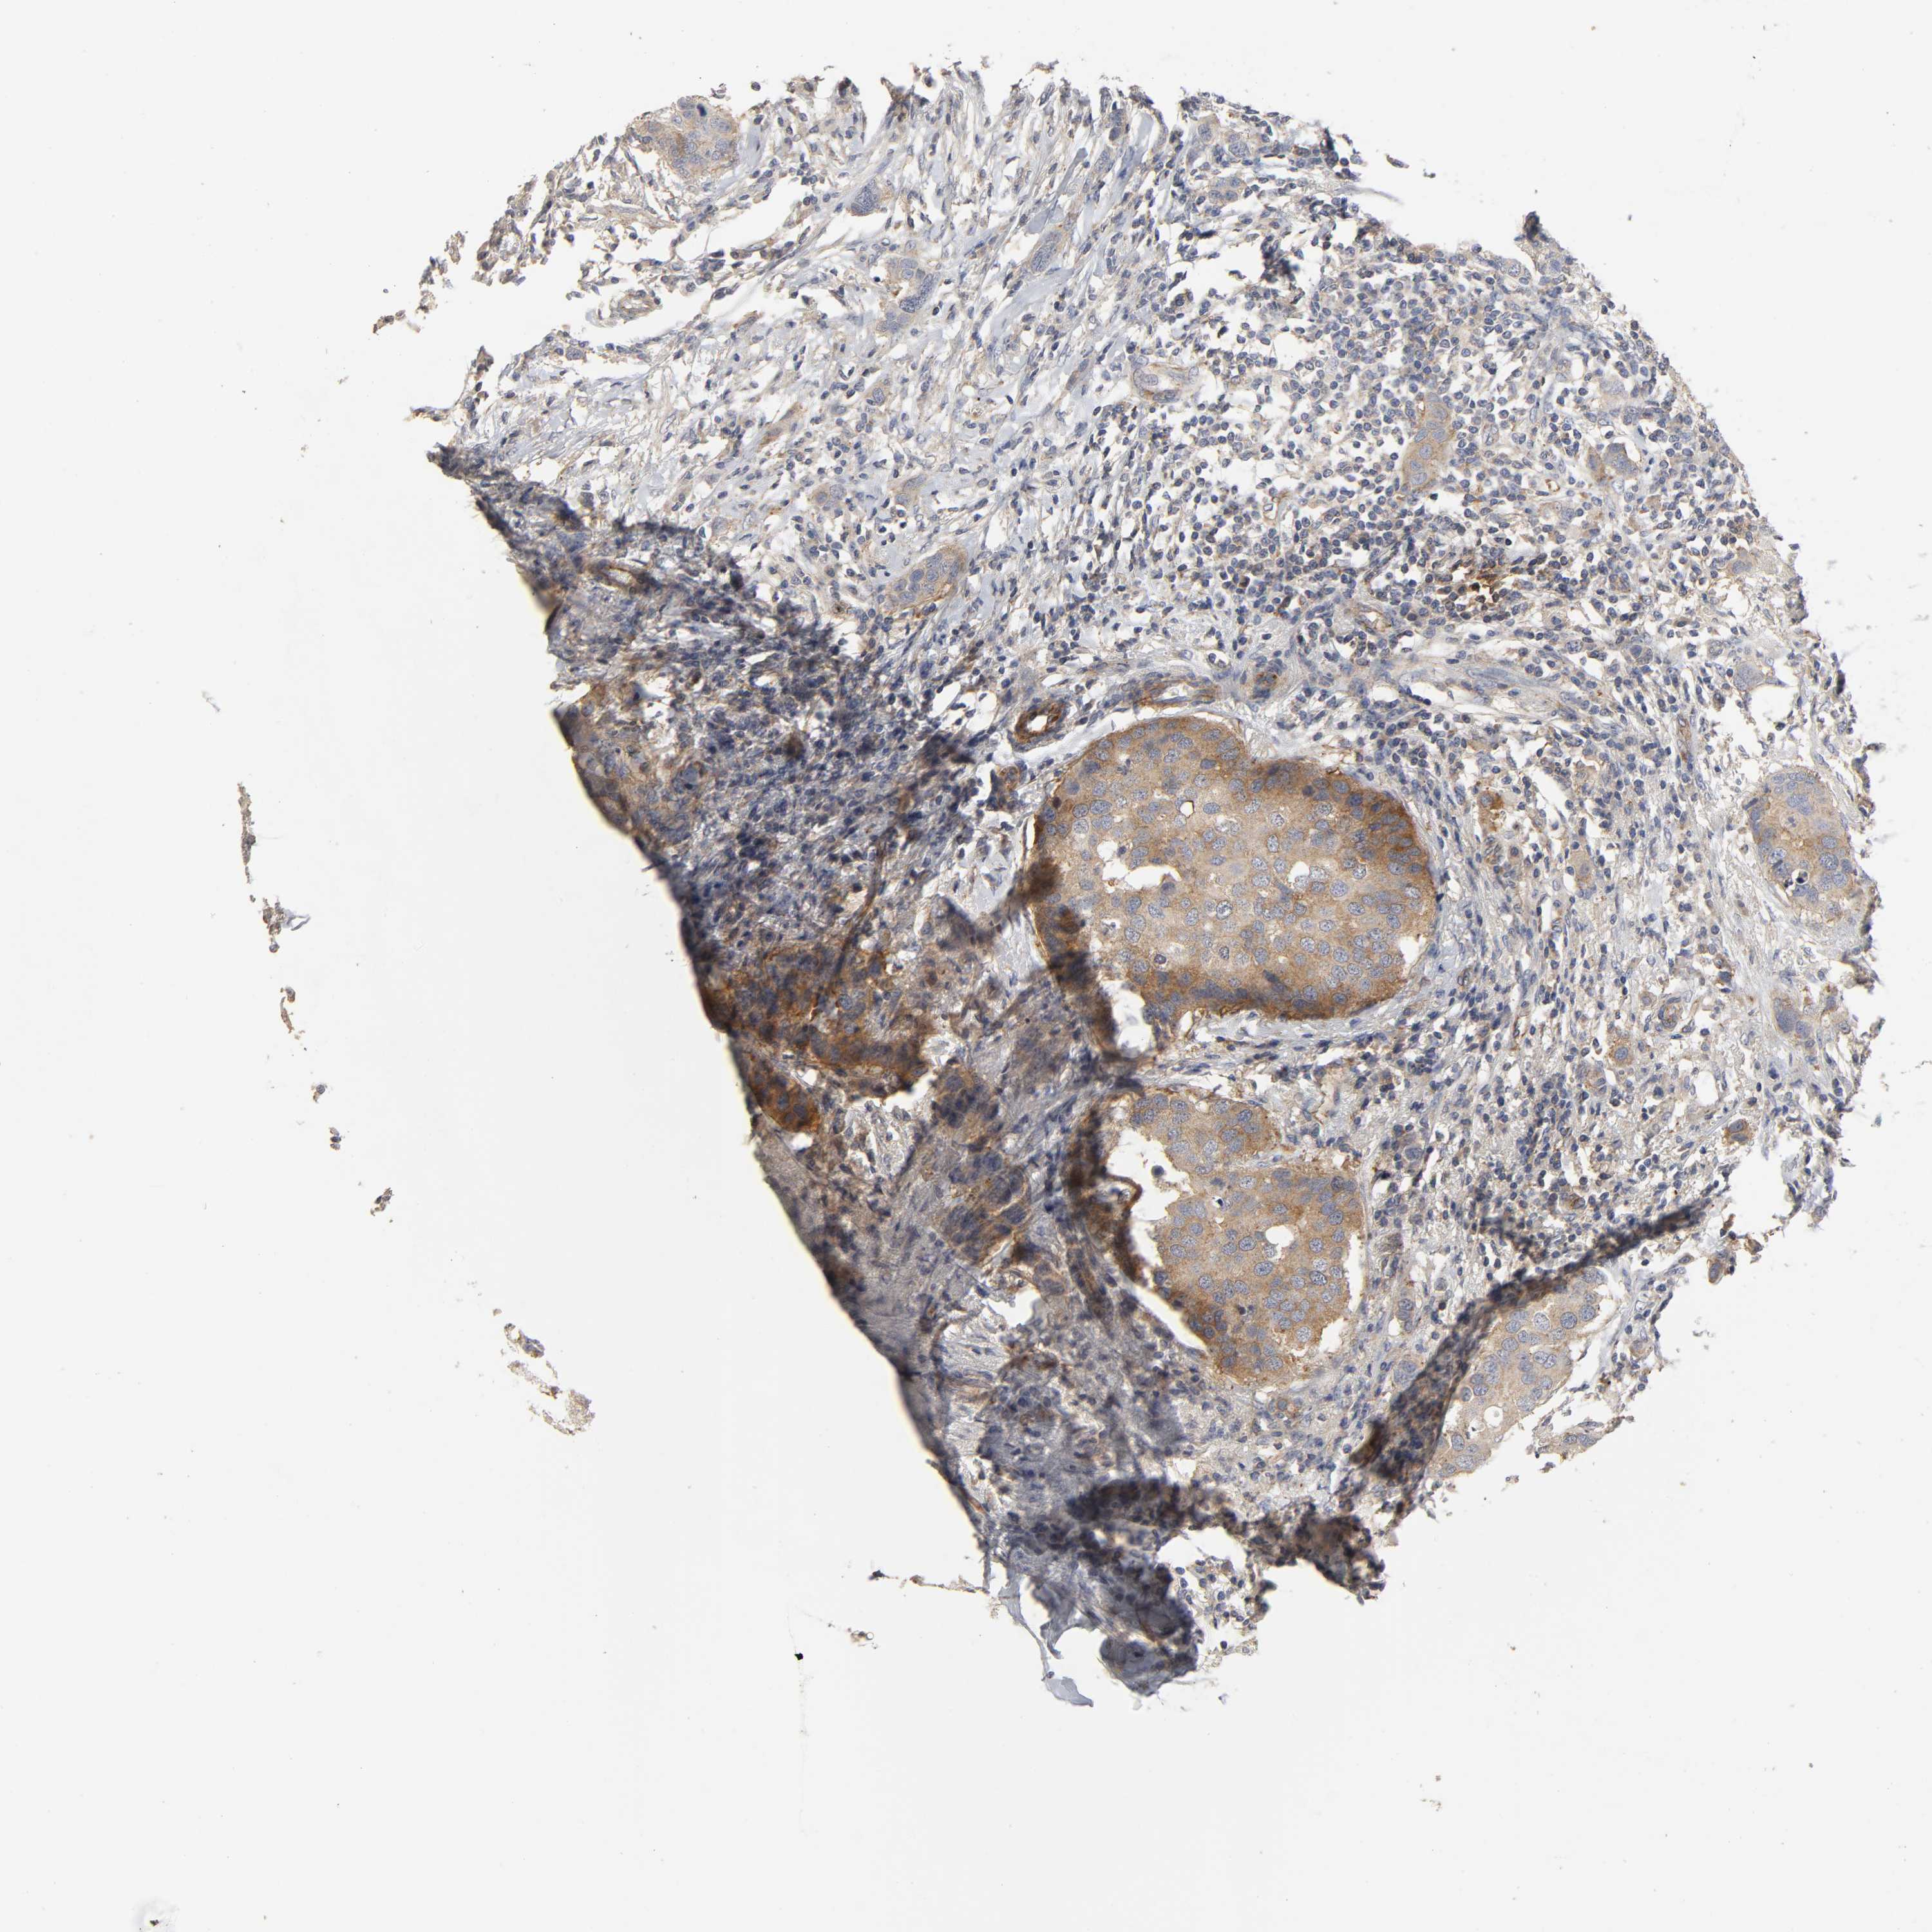

CANCER BREAST CANCER Show tissue menu

BRCA TCGA BRCA VALIDATION PROTEIN EXPRESSION

ANTIBODIES

AND

VALIDATION